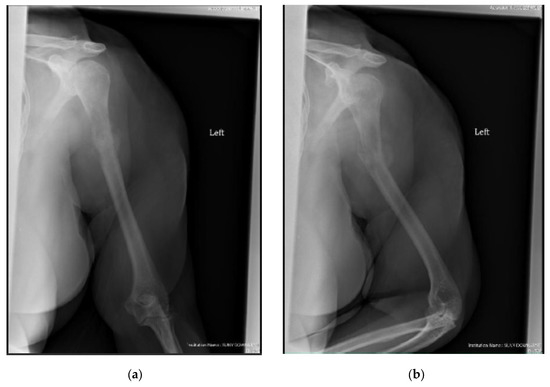

Figure 3.

(a) AP and (b) oblique left humerus radiographs of a 47-year-old female with mixed lytic sclerotic lesion in the proximal meta-diaphyseal region, with a pathologic fracture and periosteal reaction in a patient with established metastatic breast cancer. This was treated by an uncemented IMN, with three proximal locking screws and one distal screw, as shown in (c) AP and (d) oblique humerus radiographs. No cement was used, as there was enough proximal and distal bone to support the nail and the inter-locking screws, and some healing changes were already evident.